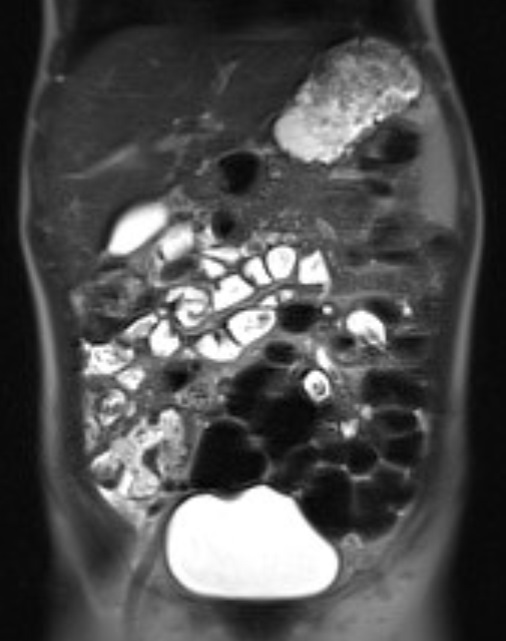

Además, se descarta afectación a lo largo del intestino delgado con la realización de enterorresonancia, que es normal.